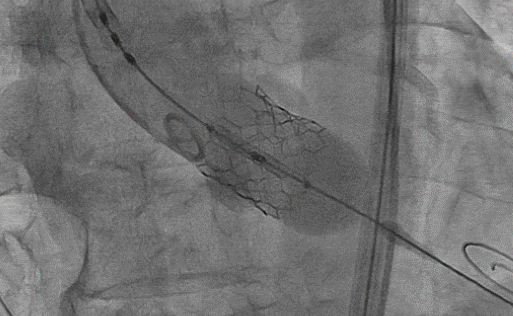

留置中